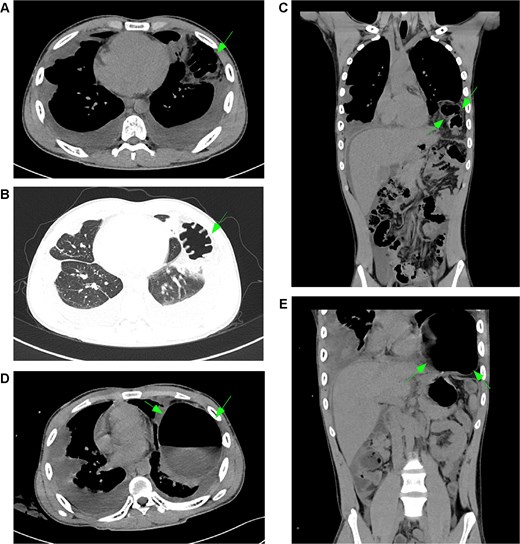

January 2025, on the premise of denying a history of blunt abdominal or chest trauma, the patient developed a left diaphragmatic hernia (Fig. 3A–C). Initially managed conservatively, the condition progressed (Fig. 3D and E), prompting laparoscopic diaphragmatic hernia repair to relieve the obstruction and reconstruct the diaphragm. Intraoperatively, a weakened diaphragmatic area was noted, with a ~ 6 × 5 cm defect (Fig. 4A). The right diaphragm appeared normal (Fig. 4B). The hernia sac was partially closed with continuous 3–0 sutures, leaving a 0.5 cm opening. After anesthesiologist-confirmed bilateral ventilation, the sac was fully closed with defect reinforcement using Burch sutures (Fig. 4C). Due to extensive diaphragmatic weakness and recurrence risk, we placed a synthetic mesh over the weakened area (Fig. 4D), then covered it with an anti-adhesive biologic mesh secured by sutures (Fig. 4E) to prevent adhesions. Postoperative imaging confirmed successful repair without adhesions (Fig. S3), with good patient recovery. At the one-month telephone follow-up, the patient was asymptomatic and reported no complaints.

Development and progression of a left diaphragmatic hernia. (A–C, arrows) January CT scan demonstrates a newly developed left diaphragmatic hernia with herniation of abdominal contents into the thoracic cavity. (D, E, arrows) Follow-up CT scan in March shows significant progression of the herniation with increased volume of herniated content and more pronounced displacement of thoracic structures. Notes: (A–C) Arrows indicate the initial presentation of the left diaphragmatic defect, showing herniation of the omentum and bowel loops. (D, E) Arrows highlight interval progression, demonstrating substantial enlargement of the hernia sac and increased mass effect on the adjacent lung parenchyma.